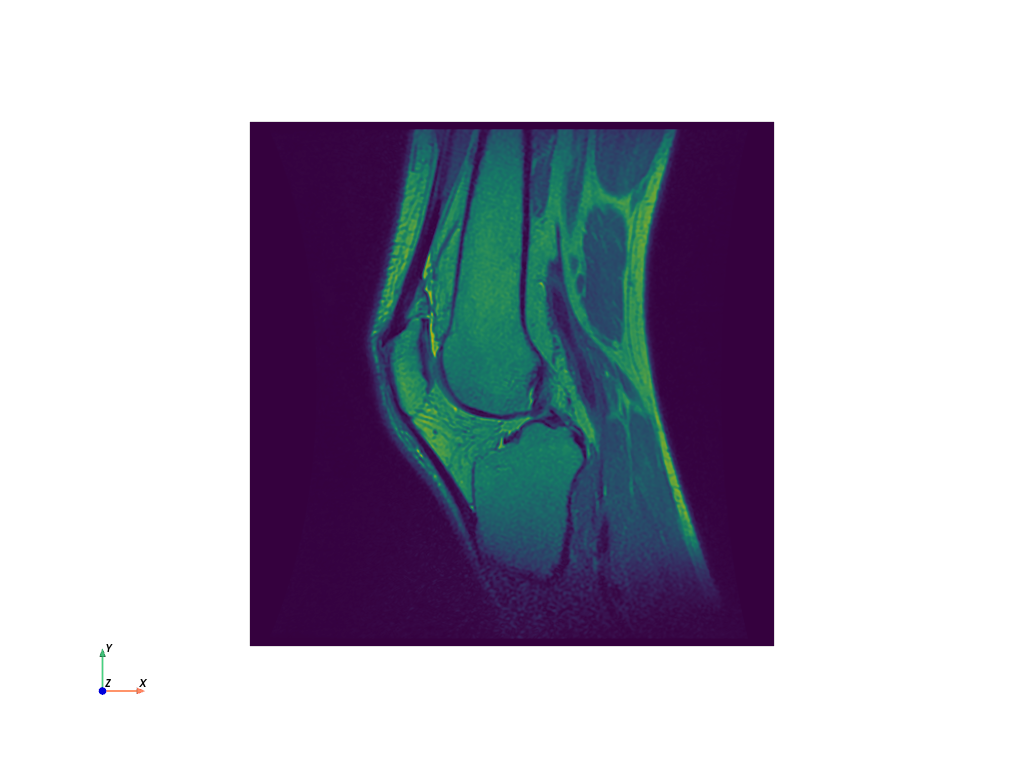

Download knee dataset.

>>> from pyvista import examples >>> dataset = examples.download_knee() >>> dataset.plot(cpos="xy", show_scalar_bar=False)